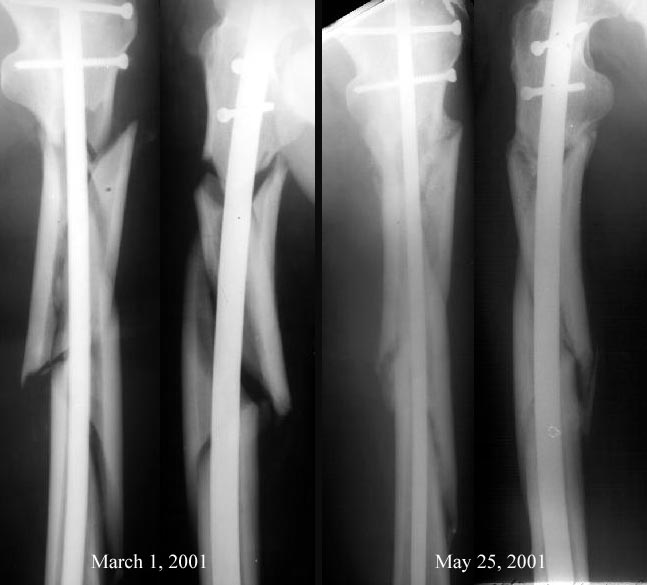

Вспоминается подобная ситуация в 2001 г., как раз сегментарный оскольчатый перелом бедра, тоже начальство упрекало в пренебрежении к принципам остеосинтеза, чуть не приказали повторно взять больного и скласть красиво все кусочки... Благодаря поддержке интернет-сообщества удалось отстоять, вскоре все замечательно срослось.

Вот картинка - после операции и через 3 мес.